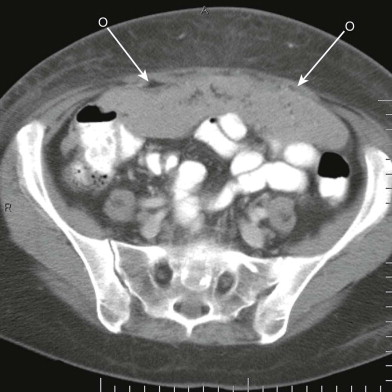

卵巣癌による腹膜播種(omental cake)

(Grainger & Allison's Diagnostic Radiology, Seventh Edition)

omental cake

(Textbook of Gastrointestinal Radiology, Fourth Edition)